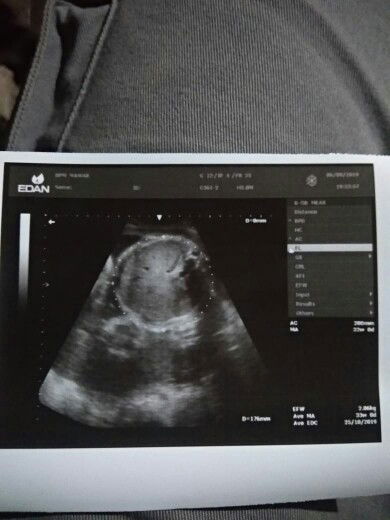

USG baby pertama ku ?

Bun ini hasil USG anak pertama ku bun dan alhamdulillah anak ku sehat bun dan air ketuban ku cukup bgt jg dng ari2 ku baik bun ....bun aku minta doanya yah kan sebentar lagi aku lahiran anak pertama ku . Aku mnta doa nya bun semoga proses persalinan ku lancar dan aku sm baby ku sehat2 bun . Makasih sebelumnya bunda?